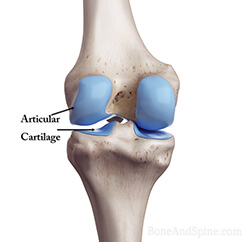

- Regenerates Cartilages

Joint Support is a powerful natural blend aiming to support your joints, mobility and flexibility. It will help you rebuild your cartilages and joint structures. The reduced inflammation in your body will protect the joint tissues. Say goodbye to the pain and discomforts that come with age, weight or athletic deterioration of the joints in the body. Improved mobility will make your life easier and happier. Feel more comfortable in your own skin every day!

Cartilages

Glucosamine Sulfate

Glucosamine Sulfate

Chondroitin Sulfate

Chondroitin Sulfate